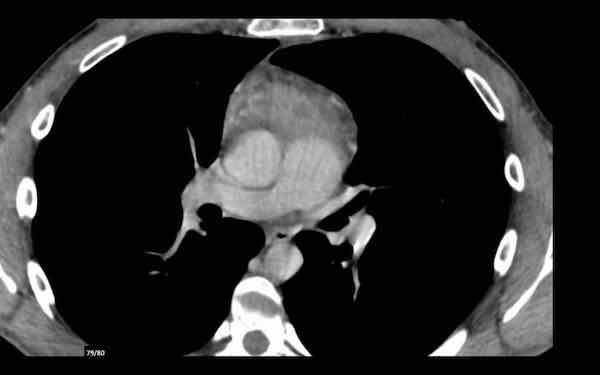

Các hình ảnh này của một phụ nữ 65 tuổi có tiền sử mắc bệnh Graves, một rối loạn tự miễn liên quan đến tình trạng cường chức năng tuyến giáp.

CT được thực hiện vì lý do ho ra máu.

Hình ảnh

Có một tuyến ức to lớn, cồng kềnh chứa mô mỡ đại thể.

Đây là hình ảnh điển hình của tăng sản tuyến ức.

Tăng sản tuyến ức trong bệnh Graves có liên quan đến tình trạng dư thừa hormone tuyến giáp và kháng thể kháng thụ thể thyrotropin.

Tình trạng này thường cải thiện sau khi điều trị thành công bệnh Graves.